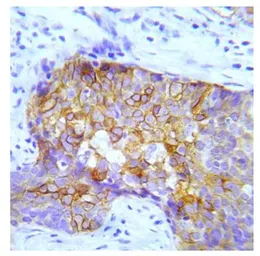

IHC-P analysis of human lung adenocarcinoma tissue using GTX79097 CRK (phospho Tyr221) antibody.